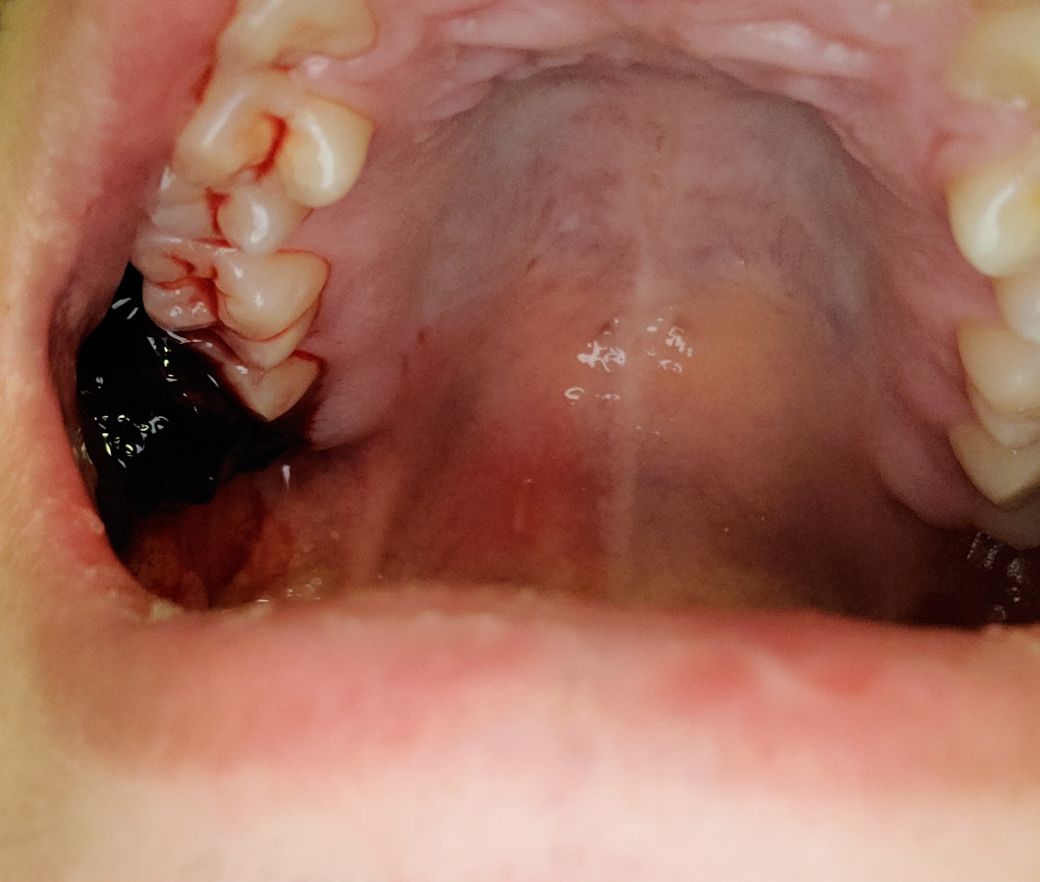

사랑니 발치 후 끈적한 피가 고인것 같은데 어떡하나요?

자고 일어나니 입에 뭐가 계속 씹혀서 봤더니 저렇네요

통증은 따로 없고 사랑니 발치한지는 2일차에요

현재 피떡이 져있는 것은 혈병으로 보이며, 이는 해당 부위 조직이 회복되는 과정으로 억지로 제거는 하지 않길 권합니다.

발치를 하고 생기는 혈병으로 보입니다

발치된 부위가 잘 치유되기 위해서는 제거 하지 않는것이 좋습다

2. 끈적한 피가 고인것은 피떡(혈전)인데 이게 잇몸 초기치유를 돕습니다 억지로 떼어내거나 그러면 치유에 방해가 됩니다 혈전이 너무 커서 불편하거나 느낌이 이상하면 멸균된 거즈로 조금 해당 부위를 눌러주시기 바랍니다

3. 별다른 통증이 없다면 이상이 있는 상태는 아닐것입니다